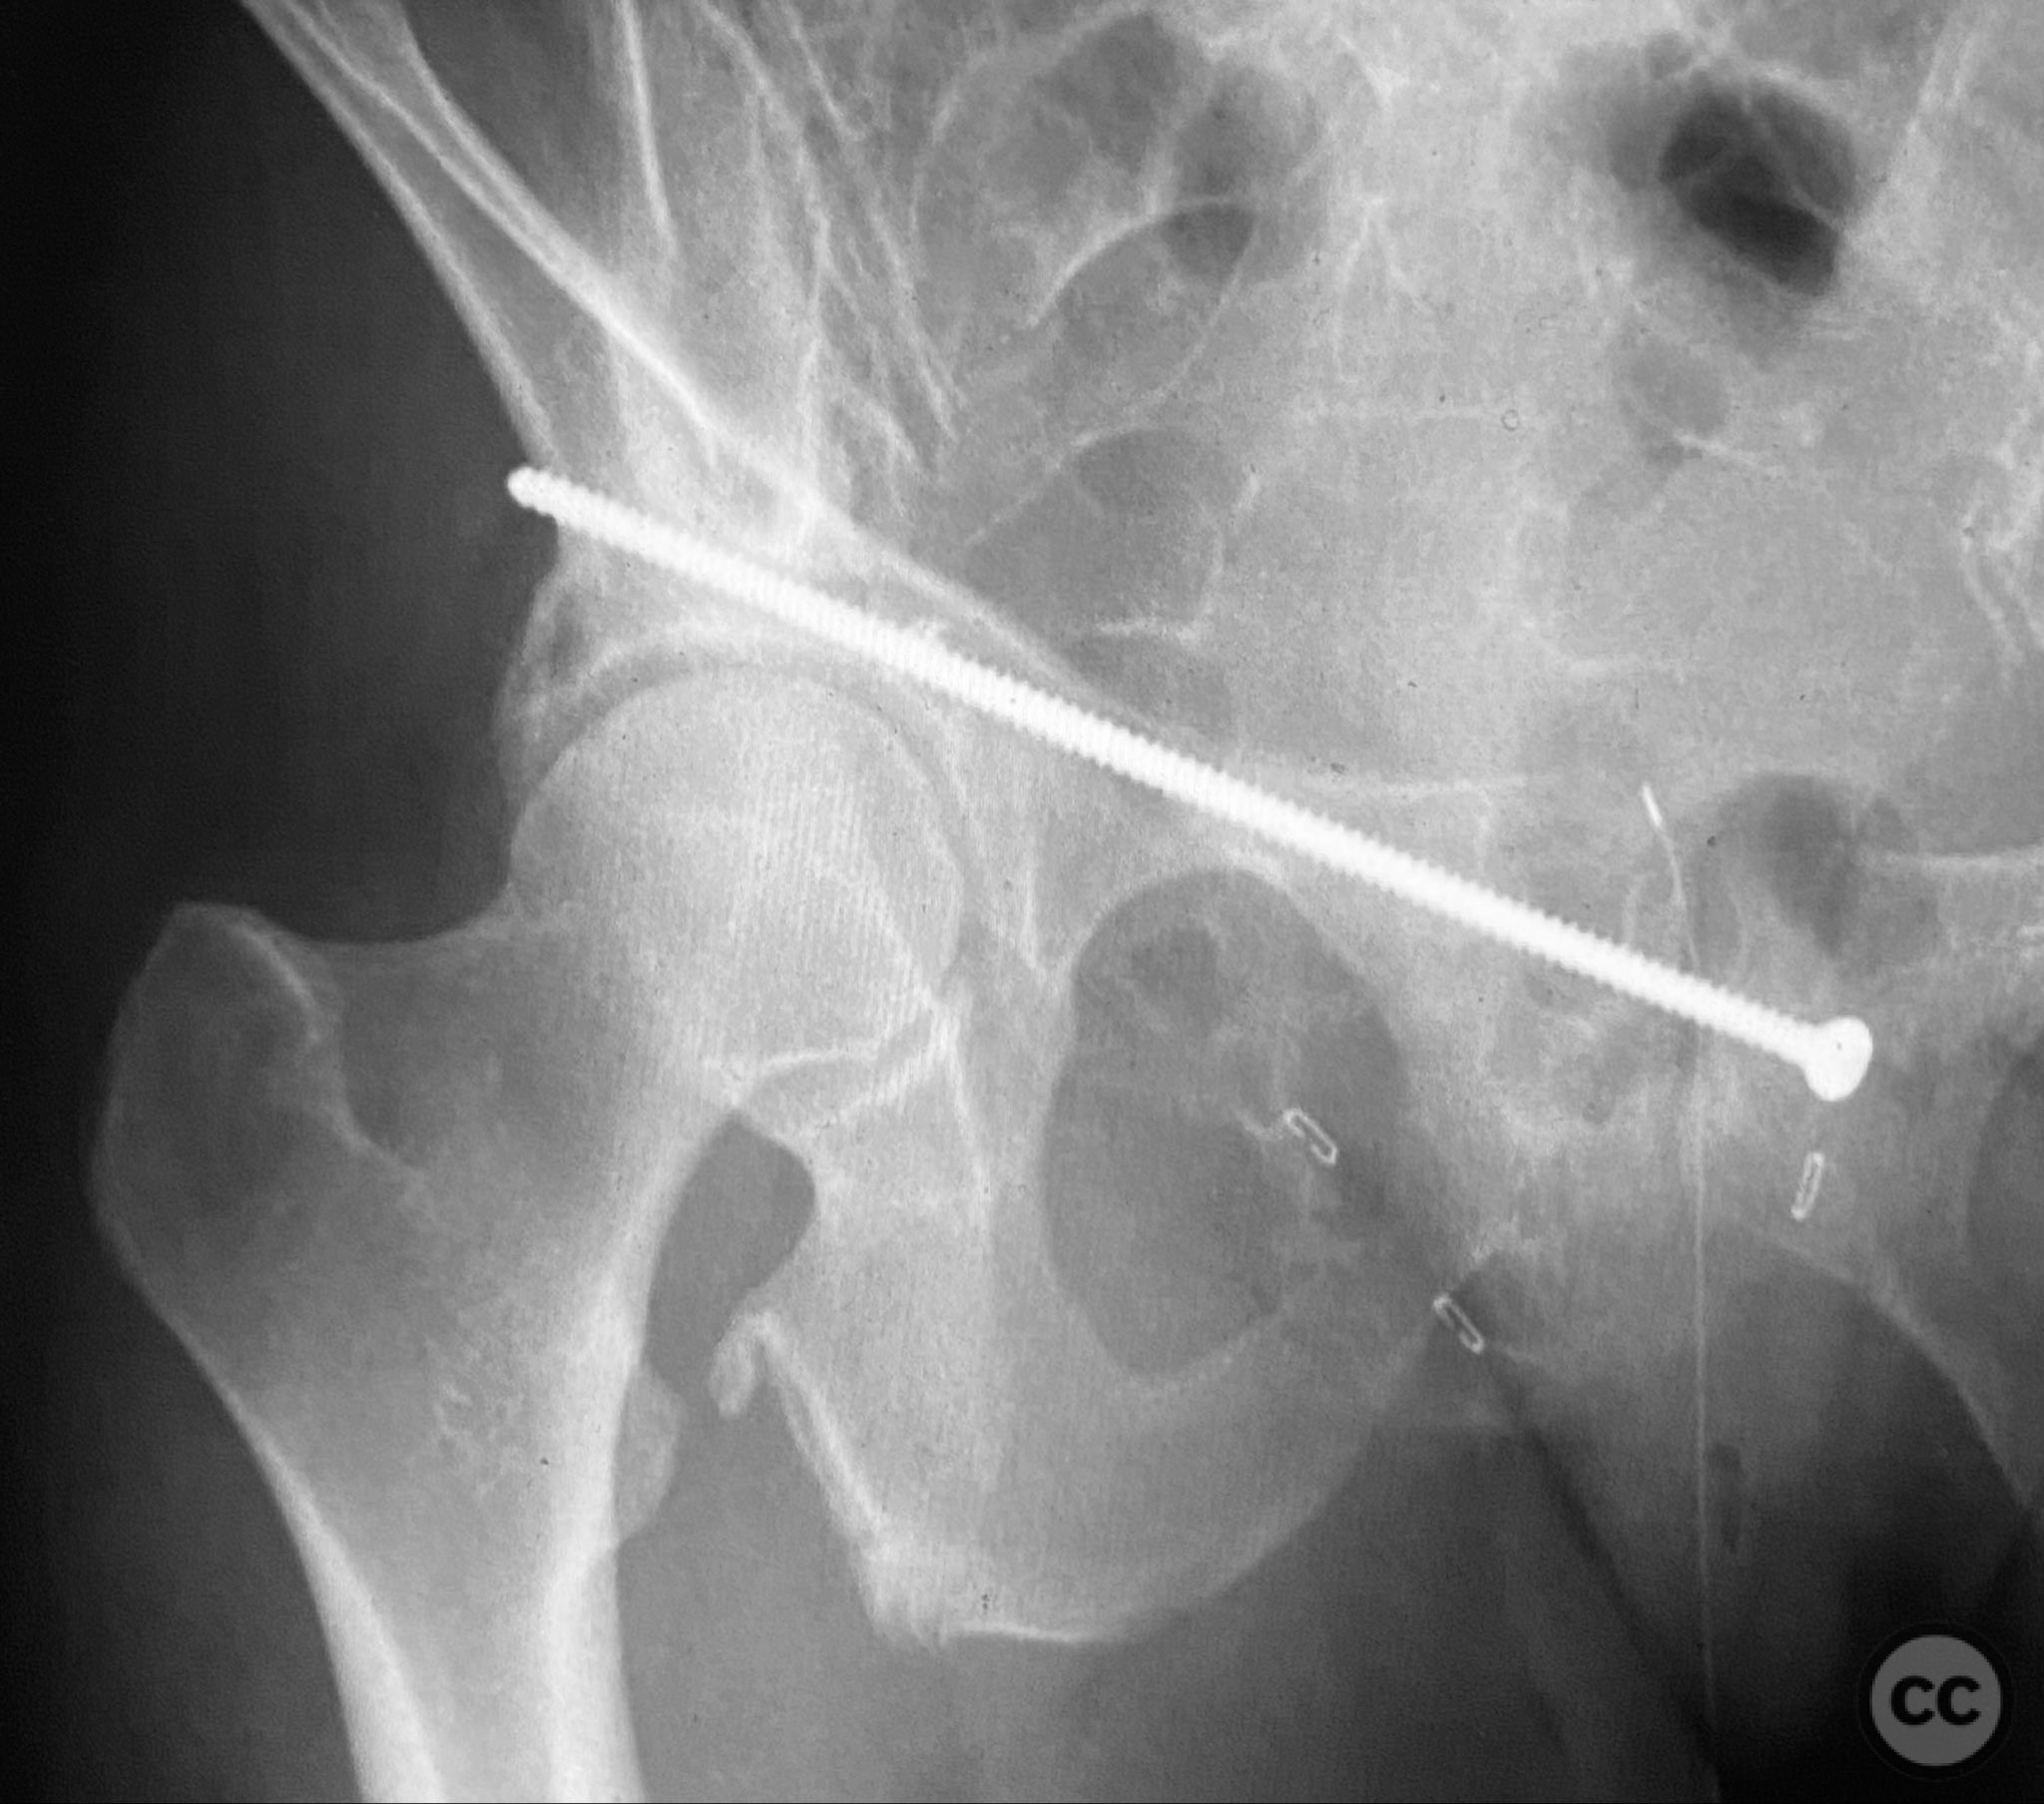

Intraoperatively, a 3.5mm drill was used through a protective sleeve to initiate the screw pathway across the superior pubic ramus. Due to poor bone quality, a 2.5mm drill was subsequently employed; however, resistance was encountered as the drill tip engaged the dense cortical apex of the anterior acetabular wall. The drill became lodged in this region. To avoid drill breakage, manual extraction using pliers was considered; however, the surgeon elected to carefully deflect and advance the drill manually, successfully completing the pathway. Screw length was measured directly from the embedded drill tip. A 4.5mm cortical screw was then inserted trans-symphyseally along the prepared medullary canal, achieving stabilization of the unstable ramus fracture. Postoperative CT confirmed appropriate screw trajectory and demonstrated the dense cortical bone at the anterior acetabular wall where the drill tip had engaged.

Orthopaedic implants used:   4.5mm cortical screw